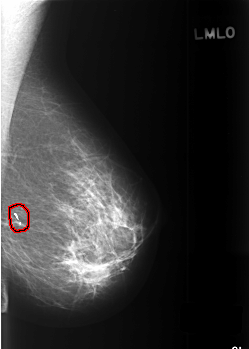

C_0381_1.LEFT_MLO

FILE: C_0381_1.LEFT_MLO.OVERLAY

TOTAL_ABNORMALITIES 1

ABNORMALITY 1

LESION_TYPE CALCIFICATION TYPE N/A DISTRIBUTION LINEAR

ASSESSMENT 2

SUBTLETY 5

PATHOLOGY BENIGN

TOTAL_OUTLINES 1

BOUNDARY